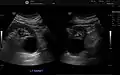

Renal cyst as seen on abdominal ultrasound